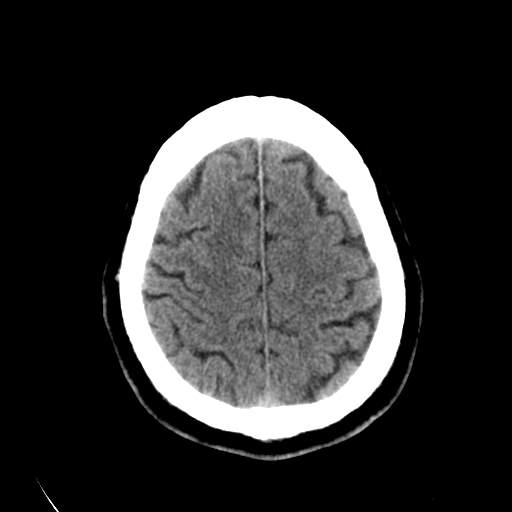

标题: CT28335:男,58岁,请各位看看是不是有脑积水,蝶窦内高密 [打印本页]

标题: CT28335:男,58岁,请各位看看是不是有脑积水,蝶窦内高密

轻度积水,蝶窦正常。

脑积水!建议行mri!

1)脑积水。2)副鼻窦炎。